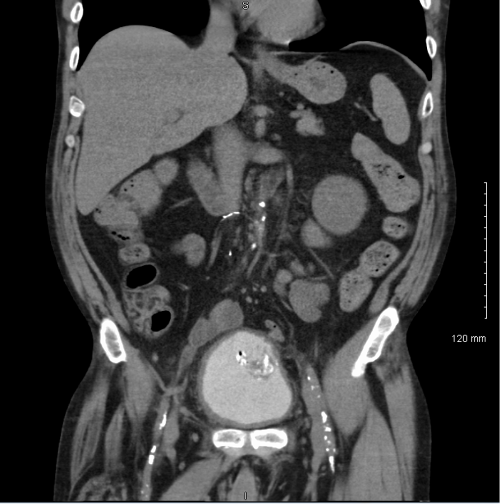

A 65 year old man presents to the emergency room with acute onset back pain. Of note, the man was diagnosed with Burkitt’s lymphoma two months prior and had recently received a course of chemotherapy. During the workup for his back pain, a chest CT is obtained and reveals a 2 cm pulmonary nodule in the left upper lobe with a surrounding “groundglass halo” highly suspicious for invasive fungal involvement. A fine needle aspiration (FNA) of the nodule is performed and tissue is sent for histopathologic examination as well as bacterial and fungal culture.